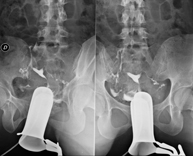

La urografia intravenosa (UIV) consisteix en l'obtenció d'imatges radiològiques seriades del ronyó, vies urinàries i bufeta. Aquest estudi requereix sempre l'ús d'un contrast iodat. - Cistografía (CUMS)

La cistouerotrografia miccional seriada consisteix en l'obtenció d'imatges radiològiques per valorar l'anatomia i la funció de la uretra i la bufeta amb l'administració de contrast iodat a través d'una sonda vesical. - Uretrocistografia (Uretro-Cums)

La uretrocistrografia retrògrada i miccional consisteix en l'obtenció d'imatges radiològiques per valorar l'anatomia i la funció de la bufeta i de la uretra. S'aplica material de contrast a través d'una petita sonda que es troba a la uretra i s'obtenen imatges durant l'ompliment i el buidatge de la bufeta. - Pielografia ascendent per catèter